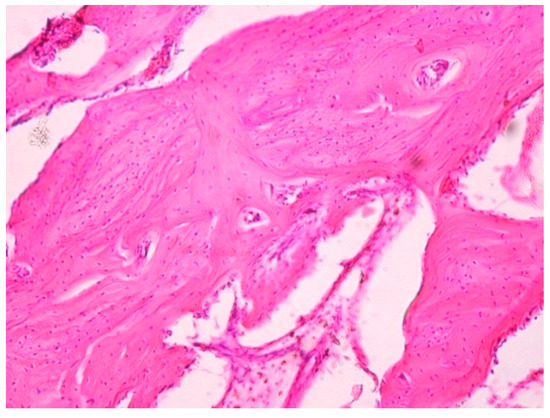

When microscopic slides of samples of the first type taken from the bone tissue of experimental animals six months after the beginning of the experiment were evaluated, the presence of a connective tissue capsule around the implant was discovered. There is a distinct layer of coarse-fibered bone (Figure 9). Some slowing of the development and formation of typical laminar bone tissue is noted.

Figure 9. Morphological pattern of the tissue surrounding an implant of the first type. Coarse-fibered bone tissue and newly formed laminar bone tissue. Six months after implantation. 400×.